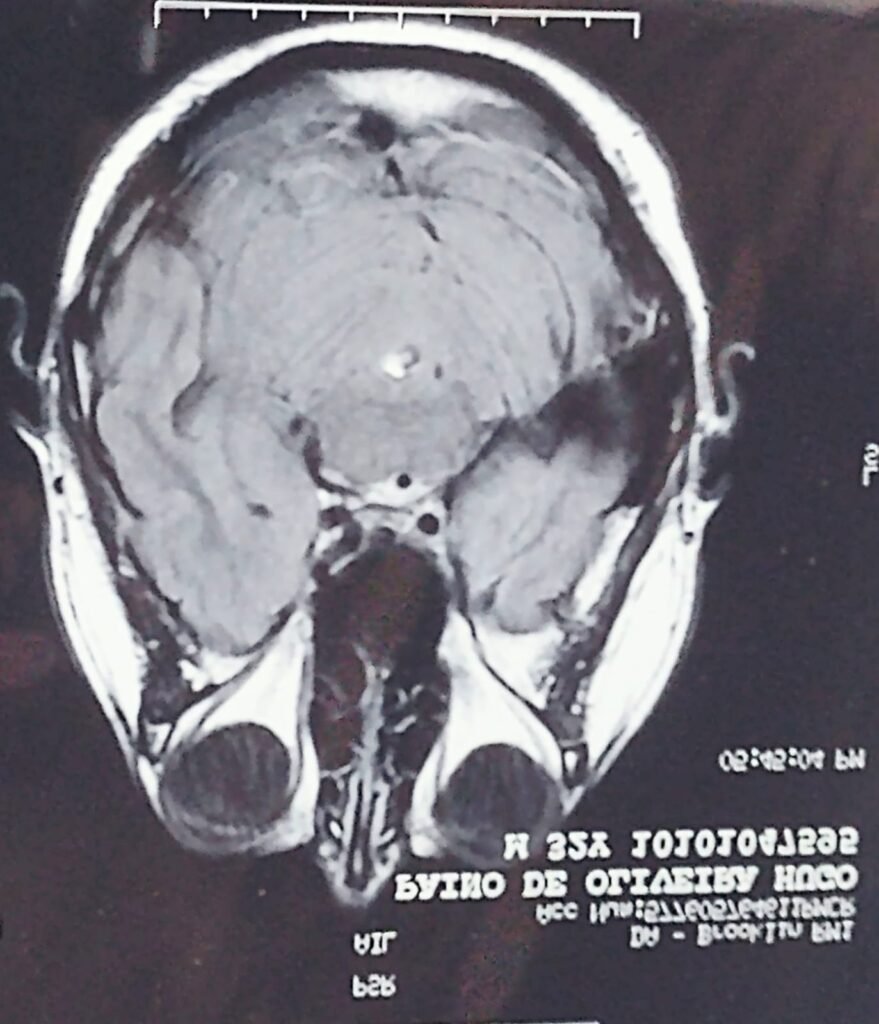

Hugo Paino de Oliveira enfrentou um dos desafios mais intensos de sua vida ao passar por três AVCs. Durante o processo de recuperação, encontrou na acupuntura uma abordagem eficaz para restaurar funções, aliviar sintomas e reconstruir sua qualidade de vida.

A trajetória de Hugo é marcada por três AVCs que poderiam ter interrompido seus sonhos, mas acabaram se tornando momentos decisivos de transformação. Cada episódio trouxe desafios intensos — dores, limitações e memórias difíceis — porém foi justamente nesse processo que ele desenvolveu uma nova consciência sobre si mesmo.